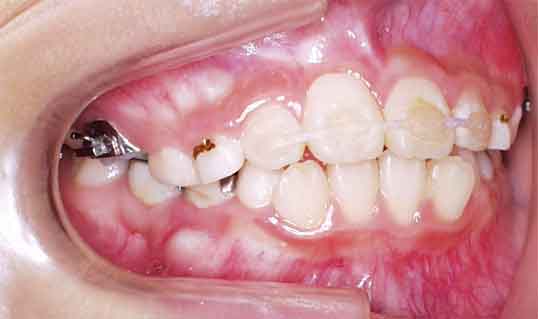

治療開始4ヶ月後